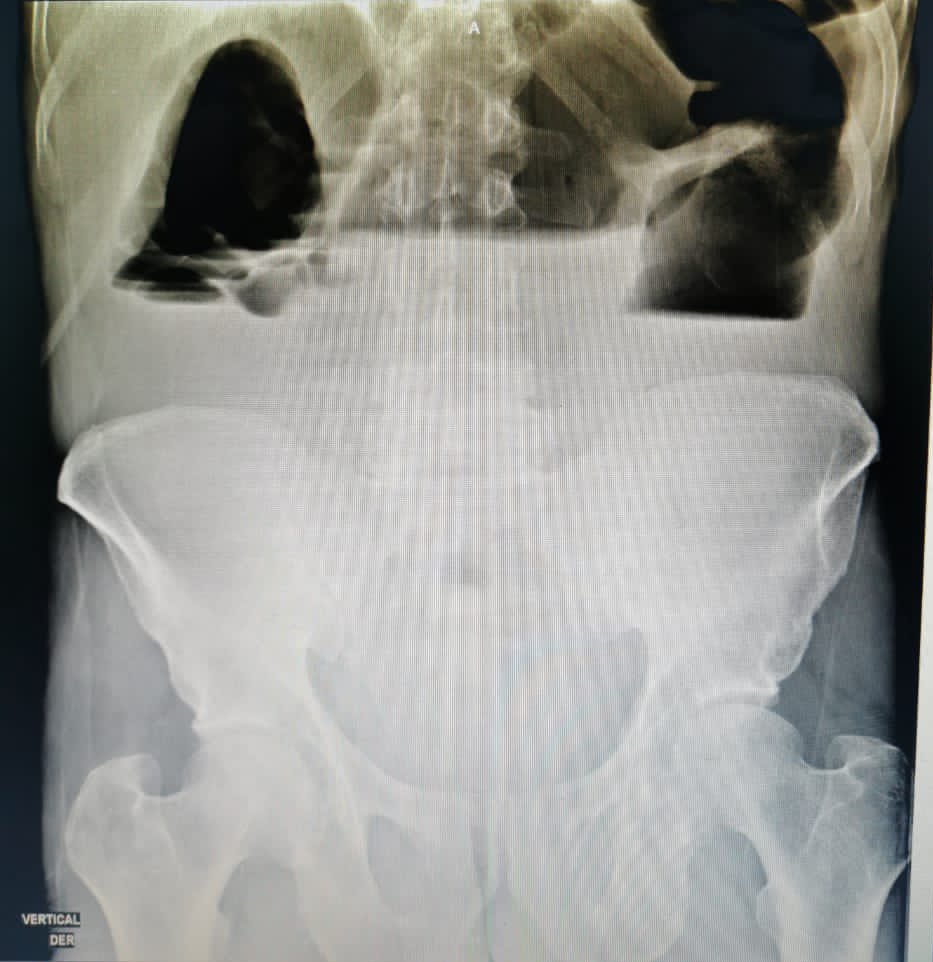

Small Bowel Obstruction: Do you still order an abdominal X-ray in the first line when you suspect a small bowel obstruction? Dr Danilo Acevedo Dr Luis Felipe Cabrera Vargas MD FACS @MISIRG1 @Cirbosque Alberto Paula Ferrada MD FACS FCCM MAMSE Cirugía Fundamental Cirugía UniCartagena #SoMe4Surgery #UISurgery